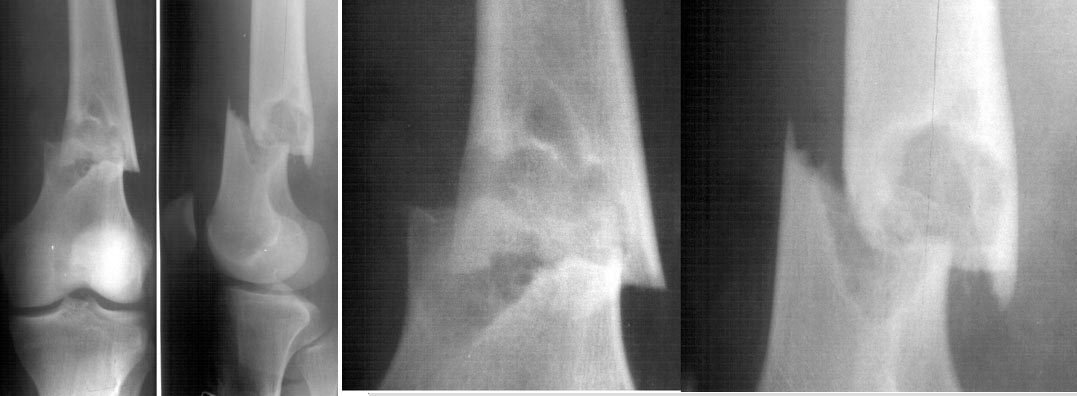

As you can remember we discussed a case of distal femoral fracture through cyst-like bone lesion. We performed closed nailing there and then had some internal discussions between different units of the institute.

Morphologists preliminary stated that it is non-ossyfying fibroma, and excluded any malignant process.

And today a next 16 y.o. male admitted to us with similar fracture pattern, but with a small focus, radiologists (and we independently) recognized the lesion as fibrous cortical defect.